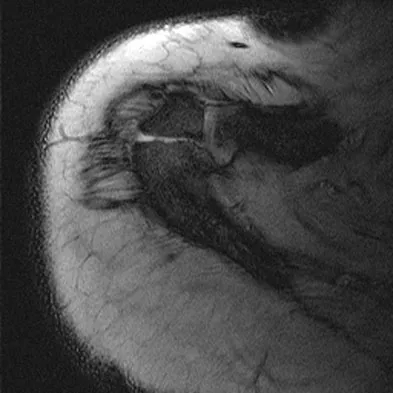

A 23-year-old man reports pain on the superior aspect of his right shoulder with repetitive overhead activities and when lying on his right side. Figure 29 shows an axial MRI scan. What is the most likely diagnosis based on the MRI findings?